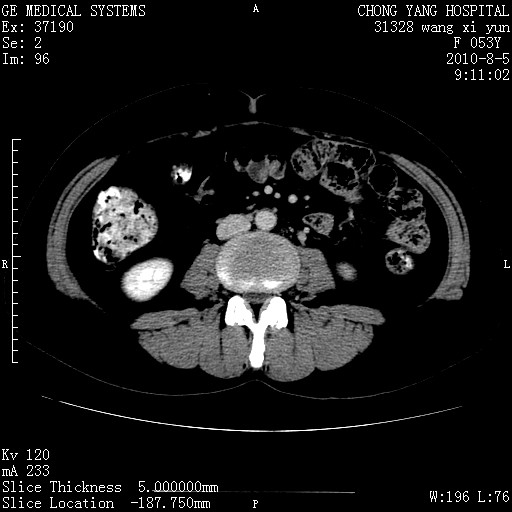

标题: CT28214:F41Y 血尿二十天,建议盆腔平扫加增强。

1)考虑肝左叶胆管细胞癌。2)脂肪肝。